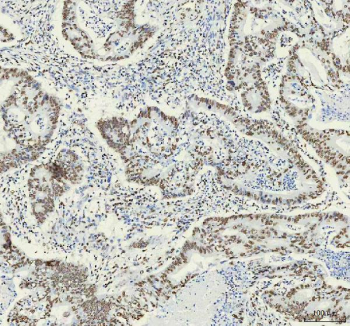

IHC analysis of HNRNPM using anti-HNRNPM antibody. HNRNPM was detected in a paraffin-embedded section of human rectal cancer tissue. Heat mediated antigen retrieval was performed in EDTA buffer (pH 8.0, epitope retrieval solution). The tissue section was blocked with 10% goat serum. The tissue section was then incubated with 1:50 rabbit anti-HNRNPM antibody overnight at 4oC. Peroxidase Conjugated Goat Anti-rabbit IgG was used as secondary antibody and incubated for 30 minutes at 37oC. The tissue section was developed using an HRP secondary and DAB substrate.